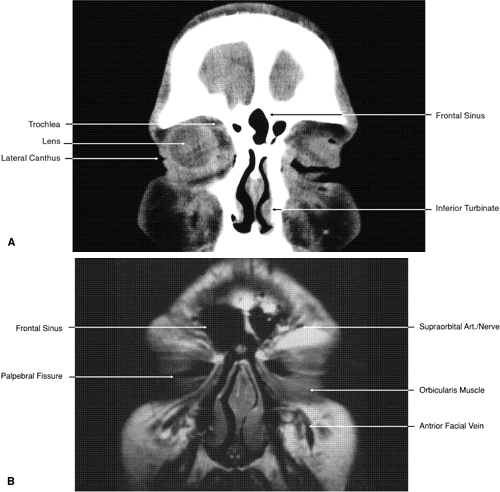

Fig. 17. Coronal images through anterior orbit. A. Computed tomography scan. B. T1-weighted magnetic resonance imaging.

Fig. 18. Coronal images through midglobe. A. Computed tomography scan. B. T1-weighted magnetic resonance imaging.

Fig. 19. Coronal images through midorbit posterior to the globe. A. Computed tomography scan.B. T1-weighted magnetic resonance imaging.